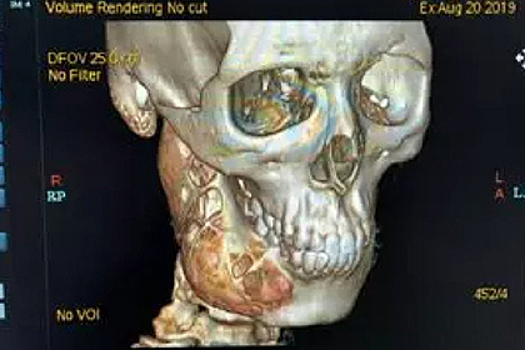

Опухоль повредила челюсть юноши из китайского города Ханчжоу, провинция Чжэцзян, который избегал зубных врачей. Об этом сообщает AsiaOne. 15-летний юноша больше года терпел зубную боль и не обращался к стоматологу. Со временем она стала такой сильной, что родственникам пришлось отвести его в больницу. Томография показала, что его зубы болели из-за амелобластомы — доброкачественной опухоли, которая поразила его нижнюю челюсть. Пока юноша медлил, в кости появились многочисленные повреждения, в том числе крупное отверстие. Чтобы удалить опухоль и восстановить поврежденную челюсть, понадобилась хирургическая операция. Родственники юноши рассчитывают, что он полностью выздоровеет. В 2018 году сообщалось, что на нижней челюсти филиппинского строителя выросла амелобластома, которая сопоставима по размерам с его черепом. Он считает, что его злоключения начались с травмы, которую он получил в юности во время игры в баскетбол.